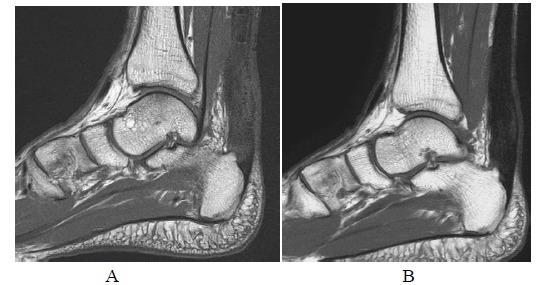

手术修复后跟腱的磁共振成像

MR Imaging of the Achilles Tendon after Surgical Repair.

Achilles tendon tear is common and increasingly frequent. Magnetic resonance imaging (MRI) is the modality of choice for radiological evaluation. It is accurate to assess the status and integrity of the tendon with well documented features. In this article, the MR findings of a normal Achilles tendon as well as common diseases like insertional and noninsertional tendinosis, chronic tendinosis with marked lengthening, tendon rupture are illustrated. After a torn Achilles tendon receives surgical repair, it undergoes different stages of healing process including inflammatory, reparative and remodeling phases. Acute scar tissue in the surgical bed may share similar MR features of tendon re-rupture especially in the early healing phase because both are T2W hyperintense. The size of the gap may even appear larger than expected on T2W images possibly due to tendon remodeling. Understanding of the healing process in post-operative period may prevent overestimation of tendon gap and misdiagnosis of re-tear. We describe the MR features of the post-operative changes with serial studies in different months after surgery. The MR findings with the highlights of the expected sequential changes in normal healing process are illustrated in different cases. A case with surgical repair on a partial tear of Achilles tendon is also included.

摘要

跟腱撕裂很常见且愈发频发。磁共振成像(MRI)是放射学评估的首选方式。它能够准确评估肌腱的状态和完整性,且具有充分记录的特征。在本文中,展示了正常跟腱的磁共振成像表现以及诸如附着点和非附着点肌腱病、伴有明显延长的慢性肌腱病、肌腱断裂等常见疾病的表现。跟腱撕裂接受手术修复后,会经历不同的愈合阶段,包括炎症期、修复期和重塑期。手术部位的急性瘢痕组织可能具有与肌腱再次断裂相似的磁共振成像特征,尤其是在愈合早期,因为二者在T2加权像上均呈高信号。在T2加权像上,间隙大小甚至可能看起来比预期更大,这可能是由于肌腱重塑所致。了解术后愈合过程可避免对肌腱间隙的高估以及对再次撕裂的误诊。我们通过对术后不同月份的系列研究来描述术后改变的磁共振成像特征。在不同病例中展示了磁共振成像表现以及正常愈合过程中预期的连续变化要点。还纳入了一例跟腱部分撕裂手术修复的病例。